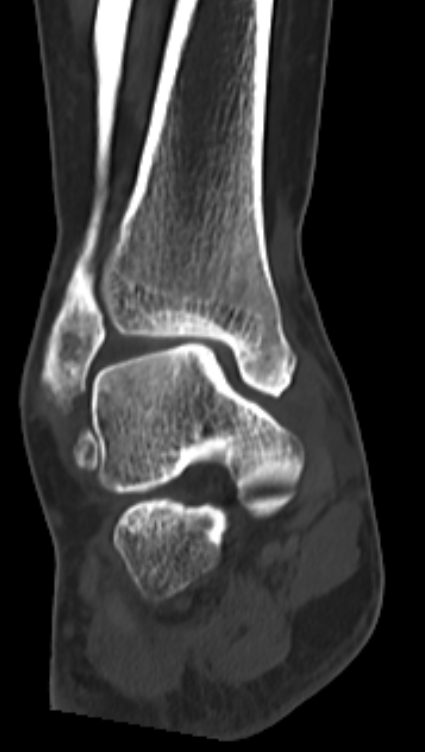

第一台手术的患者是位75岁的叔叔,被“脚脖子”痛缠了4年,疼得越来越厉害,病情已经到了严重阶段。

术前踝关节CT

武勇主任团队给他做了3D打印导板辅助下人工全踝关节置换术。

这种手术适合踝关节病严重的患者,通过替换病变的关节结构,能帮着缓解疼痛、恢复关节活动,让老人日常走路更自在些。